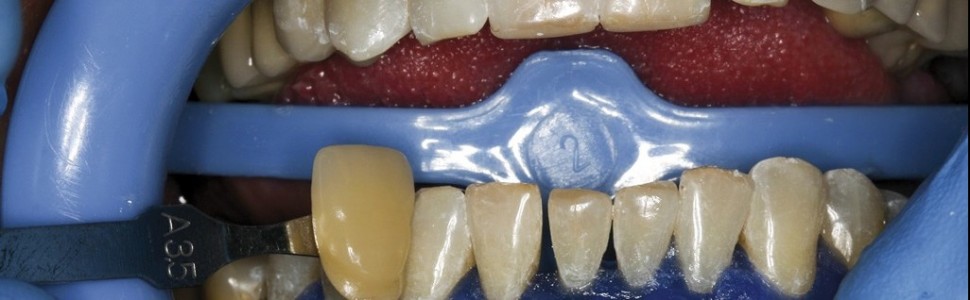

Wykorzystanie lasera diodowego w procedurze wybielania zębów z nadwrażliwością zębiny

Zastosowanie kliniczne laserów jest coraz częstsze w procedurach leczniczych. Obecnie coraz szerzej wykorzystuje się lasery niskoenergetyczne. Rosnącą popularnością cieszą się zabiegi z zakresu stomatologii estetycznej z ich użyciem. Wybielanie zębów ze zwiększoną wrażliwością zębiny stanowi problem. Znoszenie ich nadwrażliwości jest możliwe dzięki naświetlaniu okolicy szyjki zęba światłem lasera diodowego. Badania pokazują, że jest to dobra alternatywa dla leczenia z zastosowaniem środków chemicznych, a proces wybielania staje się szybszy, skuteczniejszy i przyjemniejszy dla pacjenta. Zabiegi wybielania z użyciem lasera są procedurą z zakresu stomatologii minimalnie inwazyjnej, zapewniającą wysoki efekt poprawy barwy zęba.